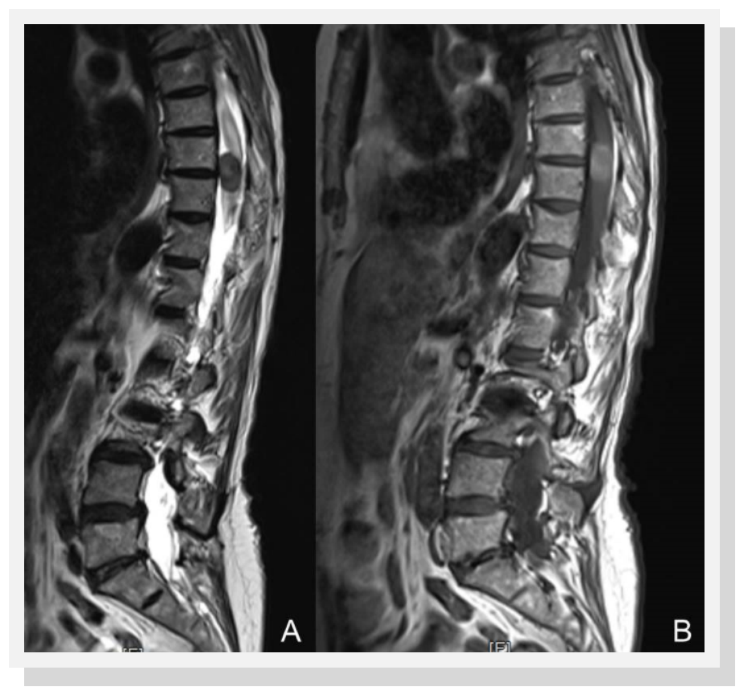

A 74-year-old woman presented complaining a several-month history of increasing thoracic back pain and left leg pain. Neurological examination demonstrated a spastic paraparetic gait and hyperreflexia of the lower limbs. Spinal magnetic resonance imaging revealed an intramedullary mass extending from T7 to T11 measuring 22 x 12 x 15 mm, slightly hyperintense on T1weighted images and hypointense on T2 weighted sequences and showed mild and heterogeneous enhancement after injection of gadolinium (Figure 1). Motor and somatosensory evoked potentials (SSEP) were recorded during surgery. A T7-T11 laminectomy and posterior midline myelotomy was performed. The exposed black and rigid tissue was removed en block (Figure 2). Gross total removal was achieved, as confirmed by MRI with and without contrast 24 hours after operation.

Figure 1.Spinal magnetic resonance imaging showing an intramedullary mass extending from T7-11 A) hypointense on T2 weighted sequences and B) slightly hyperintense on T1weighted imagines with mild and heterogeneous enhancement after the injection of gadolinium.

Typical MRI show an intramedullary lesion that appears isointense on T1-weighted sequences, hypointense on T2 weighted sequences, and enhances homogenously with gadolinium. These signal features are inconsistent due to the variable degree of tumour melanisation, which affects the signal characteristics on MRI. Hence, meningeal melanocytoma should be included in the differential diagnosis of lesions as ependymoma, meningioma and intramedullary astrocytoma 5, 6, 7.